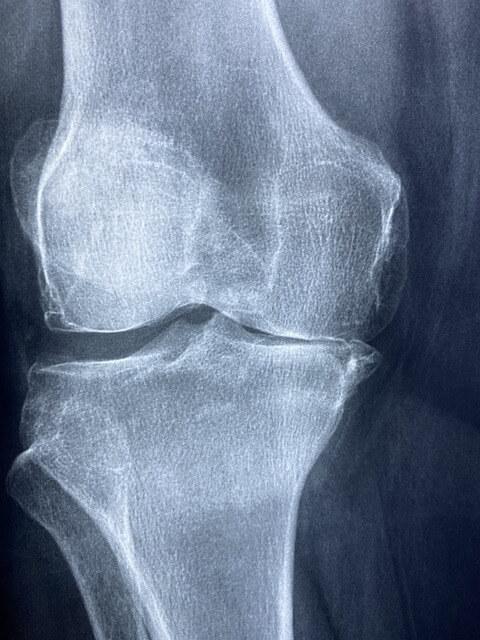

시서스는 특히 관절 및 연골 건강에 도움이 되는 것으로 알려져 있습니다. 일부 연구에 따르면, 사각 말린드나무는 관절염 및 골다공증과 같은 자주 발생하는 섬유염 관절 질환에서 두통, 염증 및 아픔 완화 도움을 줄 수 있습니다.